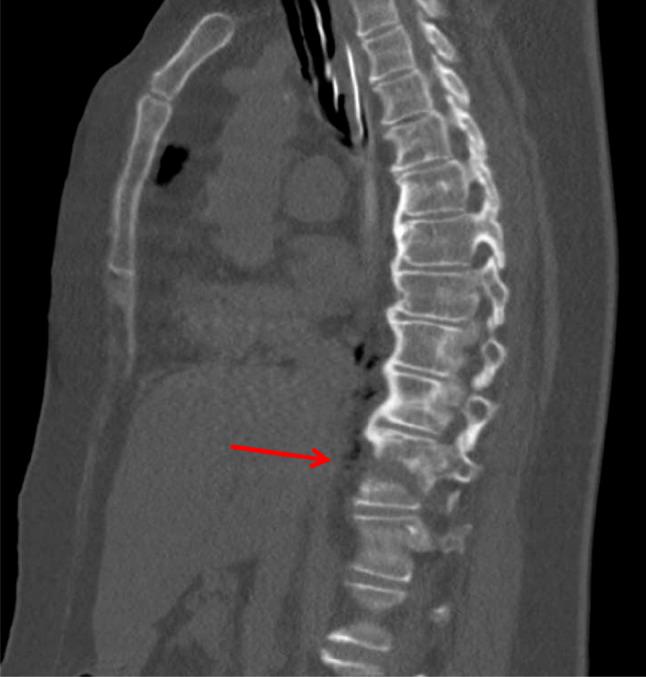

Quantitative analysis of the anterolateral ossification mass in diffuse idiopathic skeletal hyperostosis of the thoracic spine.

Diffuse idiopathic skeletal hyperostosis (DISH) is a systemic condition leading to ossification of spinal ligaments and has been shown to behave similarly to ankylosing spondylitis (AS) often leading to unstable hyperextension fractures. Currently, no quantitative data are available on the spatial relationship between the bridging anterolateral ossification mass (ALOM) and the vertebral body/intervertebral disc to explain the propensity in DISH to fracture through the vertebral body instead of through the intervertebral disc as more often seen in AS. Furthermore, no reasonable explanation is available for the typical flowing wax morphology observed in DISH. In the current study, a quantitative analysis of computed tomography (CT) data from human cadaveric specimens with DISH was performed to better understand the newly formed osseous structures and fracture biomechanics. Additionally, the results were verified using computed tomography angiography data from ten patients with DISH and ten controls. Transverse CT images were analyzed to obtain ALOM area and centroid angle relative to the anteroposterior axis; intervertebral disc and adjacent cranial and caudal levels. The ALOM area at the mid-vertebral body level averaged 57.9 ± 50.0 mm(2); at the mid-intervertebral disc space level it averaged 246.4 ± 95.9 mm(2). The mean ALOM area at the adjacent level caudal to the mid-vertebral body level was 169.6 ± 81.3 mm(2); at the adjacent cranial level, it was 161.7 ± 78.2 mm(2). The main finding was the significant difference between mean ALOM area at the mid-vertebral body level and other three levels (p < 0.0001). The subsequent verification study showed the presence of vertebral segmental arteries at the mid-vertebral body level in nearly all images irrespective of the presence of DISH. A larger area of ALOM seemed associated with increased counter-clockwise rotation (away from the aorta) of the centroid relative to the anteroposterior axis. The results from the present study suggest a predisposition for fractures through the vertebral body and a role for the arterial system in the inhibition of soft tissue ossification.